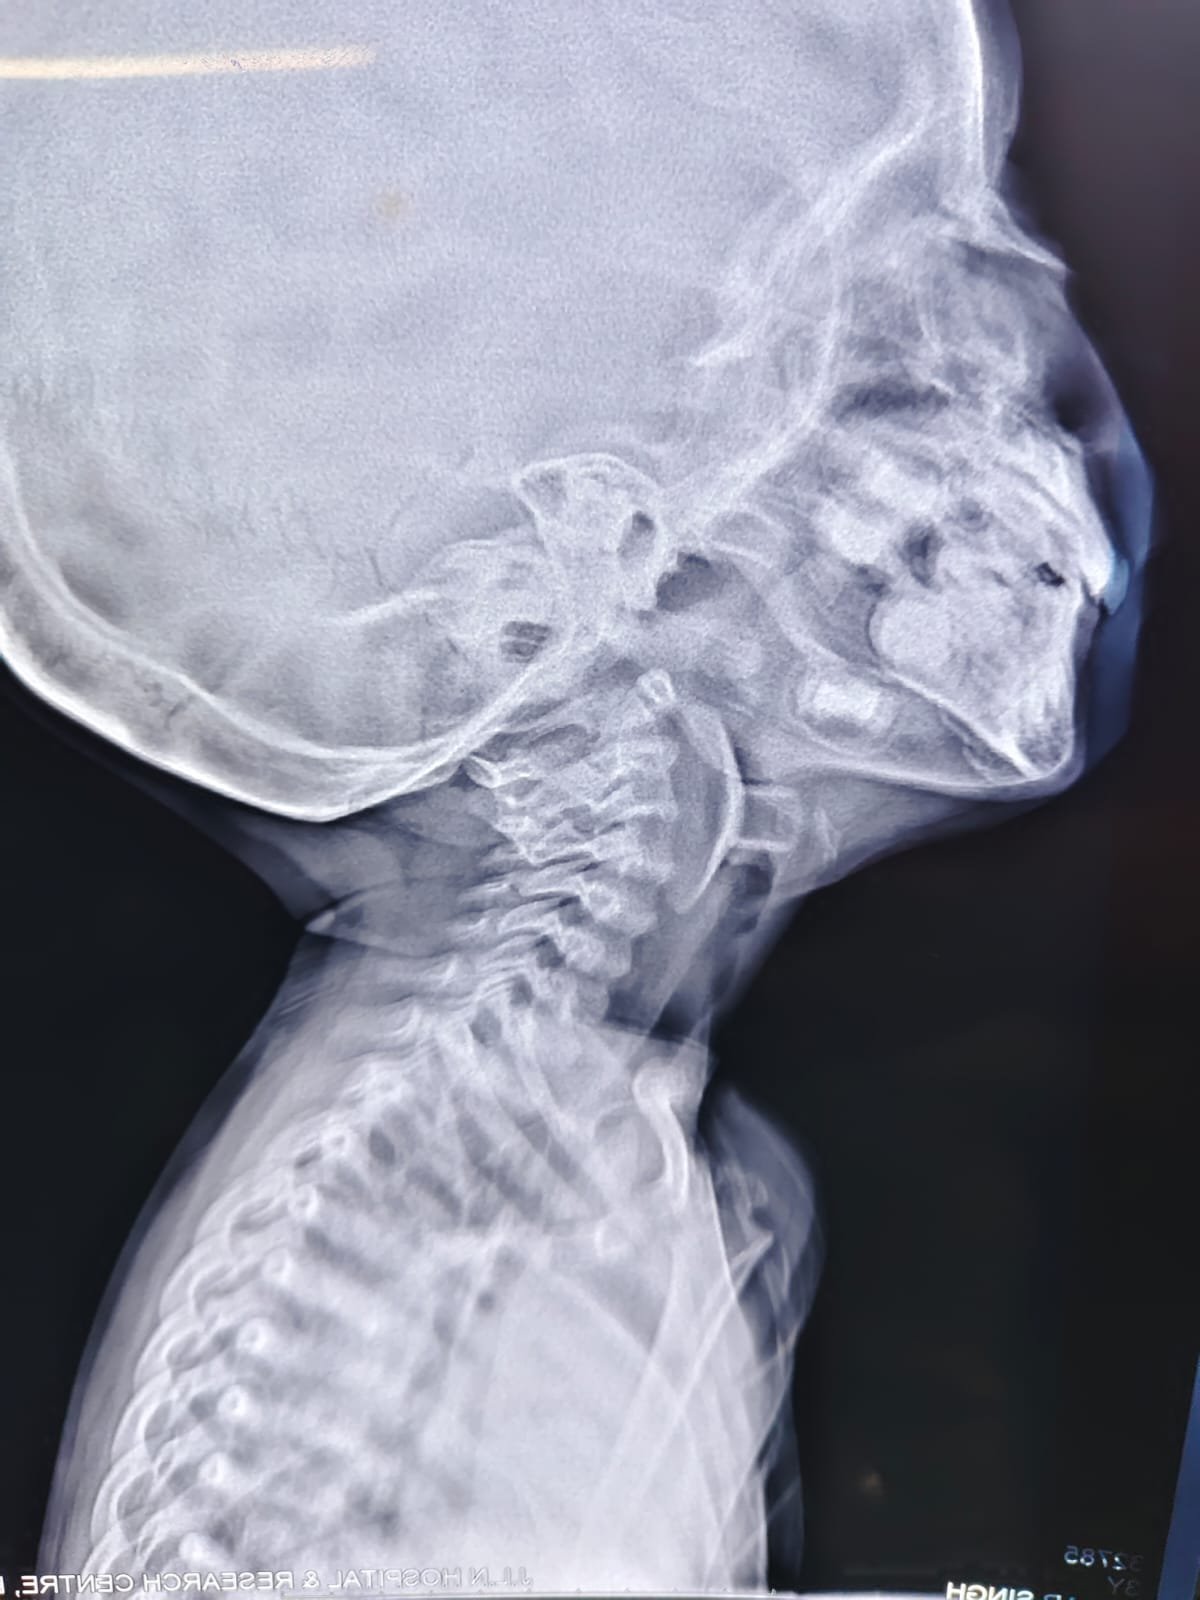

आपातकालीन विभाग में जांच के बाद पता चला कि बच्चे के श्वसन मार्ग में एक सक्शन कप एरोहेड टिप (जो आमतौर पर तीर-कमान सेट खिलौने का हिस्सा होती है) फंसी हुई थी। यह वस्तु बच्चे की जान के लिए सीधा खतरा बन चुकी थी। बिना देर किये उसे पीडियाट्रिक आईसीयू में भर्ती कर स्थिर किया गया और ईएनटी आपातकालीन ऑपरेशन थियेटर ले जाया गया।

वहाँ मुख्य चिकित्सा अधिकारी प्रभारी (चिकित्सा एवं स्वास्थ्य सेवाएं) डॉ. विनीता द्विवेदी के मार्गदर्शन में— डॉ. तनुजा और डॉ. अबानी की एनेस्थीसिया टीम ने अत्यंत नाजुक स्थिति में बच्चे के श्वसन नियंत्रण और एनेस्थेटिक प्रबंधन की जिम्मेदारी संभाली। इस बीच डॉ. अश्विन अशोक जैसवाल के नेतृत्व में (ईएनटी सर्जिकल टीम) की डॉ. प्रियंका, डॉ. रौशन और डॉ. गिरिधर के सहयोग से, डॉ. प्राची मेने के पर्यवेक्षण में बाह्य वस्तु (फॉरेन ऑब्जेक्ट) को सावधानीपूर्वक बाहर निकाला गया। कुछ ही पलों में बच्चे की सांसें सामान्य होने लगीं और माता-पिता की आँखों से राहत के आँसू बह निकले।